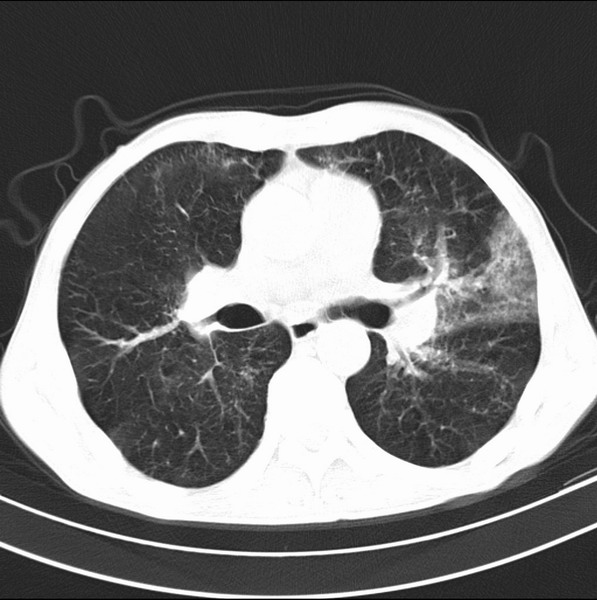

标题: CT19600:能否诊断为转移?

女、55

3年前盲肠癌、一年半前诊断膀胱癌,现在呼吸困难,临床考虑为肺转移

请问胸部ct如何诊断?能否排除淋巴管炎,纵隔窗没有问题。

未发现确切,暂时考虑炎症,建议抗炎治疗后复查

考虑间质性病变,癌性淋巴管炎可能.

转移,癌性淋巴管炎。

炎性并间质纤维化

炎性并间质纤维化,请询问病史,如用过平阳霉素或其他化疗药.可能为药物引起的间质纤维化.